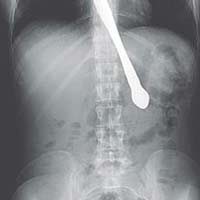

Sự việc xảy ra khi cụ Zhang Qishan (82 tuổi) đang uống sữa thì không may nuốt phải hàm răng giả vào cổ họng khiến cụ ngay lập tức bị mắc nghẹn và khó thở.

Theo bà Ahchun, ông Qishan bị một loạt các vấn đề về sức khỏe, ông cũng bị suy tim và khó thở. Một tháng trước khi qua đời, ông Qishan gặp phải tình trạng chán ăn và khó nuốt khiến ông lão chỉ còn 35kg.